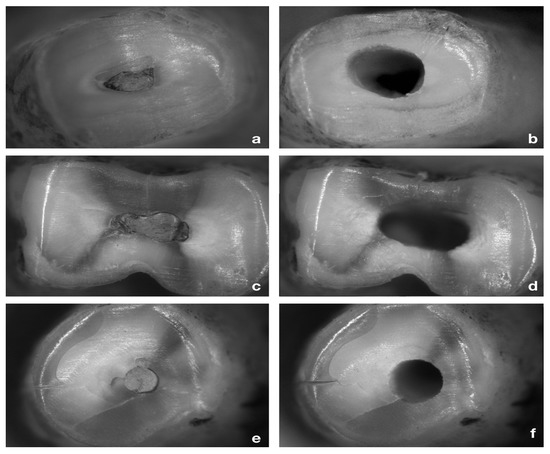

2.6. Retrograde Cavity Evaluation

3.3. Quality of the Retrograde Cavity